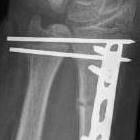

Operative management

Algorithm

1. Anatomical ORIF of distal radius with dynamic compression plate

- anatomical reduction

- restoration of radial bow

- compression for healing

Radius ORIF with dynamic compression plates

Sukpanichyingyong et al J Clin Orthop Trauma 2023